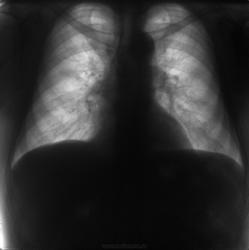

Флюорограммы в динамике. Последние две - прямая и боковая в 2012 г.

В феврале 2012 года при очередном флюрографическом обследовании были обнаружены изменения в лёгких. По собственной инициативе было сделано КТ лёгких.